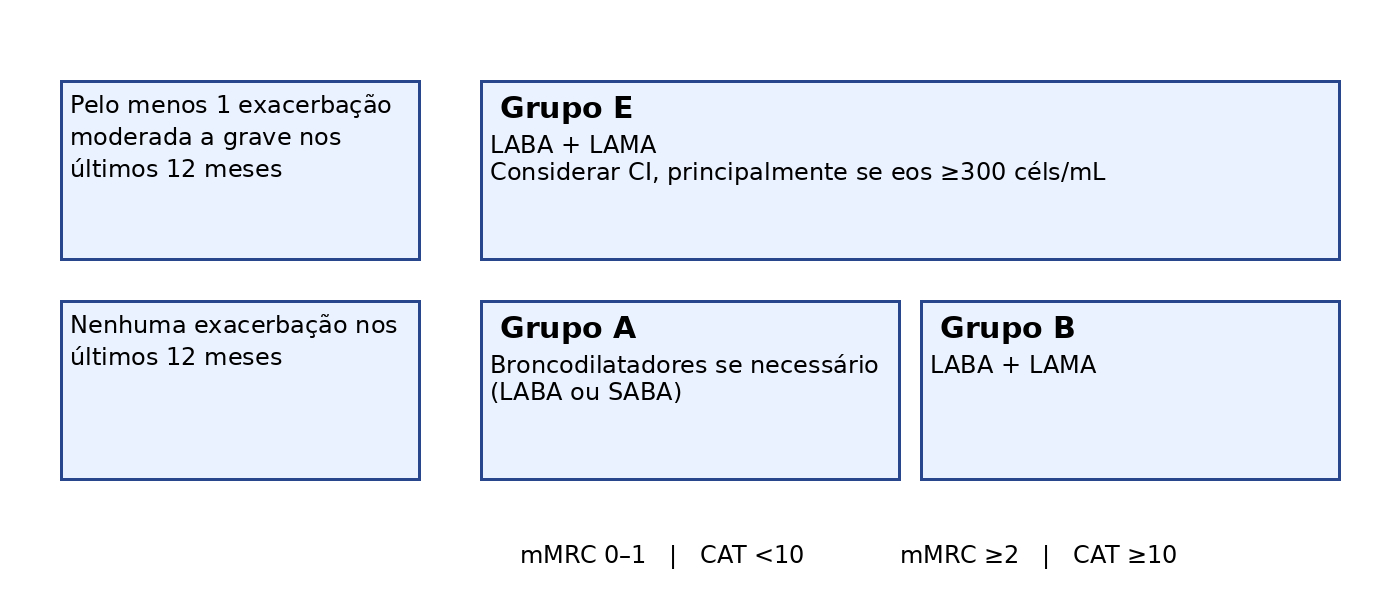

Uma das principais alterações em relação ao GOLD 2025 é a mudança do limiar de exacerbações que coloca o paciente no grupo E: antes eram pacientes com 2 ou mais exacerbações moderadas nos últimos 12 meses ou 1 hospitalização por exacerbação da DPOC, atualmente basta 1 exacerbação moderada a grave nos últimos 12 meses para ser considerado um paciente exacerbador. Exacerbação moderada é a que necessita de antibiótico e/ou corticoide sistêmico, além de ajuste de broncodilatadores de curta duração. Atualmente entendemos que mesmo uma exacerbação nos últimos 12 meses, mesmo sem necessidade de hospitalização, representa atividade de doença na DPOC, aumenta o risco de eventos adversos futuros e esse paciente tem maior risco de piores desfechos do que o paciente sem exacerbações no mesmo período. O objetivo é atingir um estado de baixa atividade, ou seja, de zero exacerbações.

Tabela adaptada do GOLD 2026